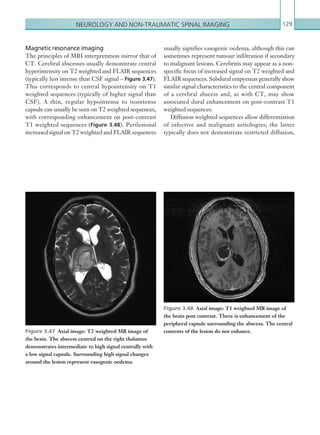

within an acute theatre complex/emergency room that

provides surgical and anaesthetic support to acutely